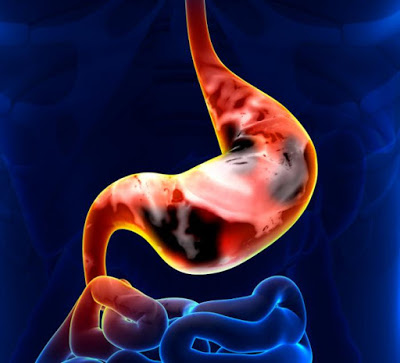

Καρκίνος στο στομάχι, τα έξι “αθώα” πρώιμα συμπτώματα. Ο καρκίνος του στομάχου είναι μία νόσος κατά την οποία τα στομαχικά κύτταρα γίνονται κακοήθη (καρκινικά) και αυξάνονται ανεξέλεγκτα, σχηματίζοντας όγκο. Πρόκειται για την πέμπτη πιο διαδεδομένη μορφή καρκίνου στην Ευρώπη. Τέταρτη παγκοσμίως και έβδομη στην χώρα μας. Προσβάλλει συχνότερα τους άντρες συγκριτικά με τις γυναίκες και συνήθως σε ηλικίες μεταξύ 60-80 ετών.

Ο γαστρικός καρκίνος δυστυχώς στην πρώιμη φάση του συνήθως είναι ασυμπτωματικός και ανακαλύπτεται τυχαία όταν η γαστροσκόπηση γίνεται για άλλα προβλήματα.

Αργότερα αρχίζει να εμφανίζει συνηθισμένα επιγαστρικά ενοχλήματα γαστρίτιδας και μόνο μια ανεπαίσθητη μικροσκοπική απώλεια αίματος (σιδηροπενική αναιμία) για πολύ καιρό πριν διαγνωσθεί. Έτσι συχνά όταν γίνεται η διάγνωση, ο καρκίνος βρίσκεται σε προχωρημένο στάδιο ή έχει κάνει μετάσταση. Κάτι που αποτελεί τον κύριο λόγο για την πτωχή πρόγνωση του. Η μετάσταση εμφανίζεται στο 80-90% των ατόμων με καρκίνο του στομάχου. Με ποσοστό επιβίωσης της τάξεως του 65% στο εξάμηνο σε αυτούς που διαγνώστηκε σε πρώιμο στάδιο και λιγότερο από το 15% σε αυτούς που διαγνώστηκε σε προχωρημένο στάδιο.

Όπως με κάθε καρκίνο, η θεραπεία είναι προσαρμοσμένη να ταιριάζει στις ανάγκες κάθε μεμονωμένου ατόμου και εξαρτάται από το μέγεθος. Την τοποθεσία και την έκταση του όγκου, το στάδιο της ασθένειας, και τη γενική κατάσταση υγείας. Ο καρκίνος του στομάχου είναι δύσκολο να θεραπευτεί εκτός αν βρίσκεται σε πρώιμο στάδιο. Δυστυχώς, λόγω του ότι ο πρώιμος καρκίνος του στομάχου προκαλεί λίγα συμπτώματα, η νόσος είναι συνήθως προχωρημένη όταν γίνει η διάγνωση.